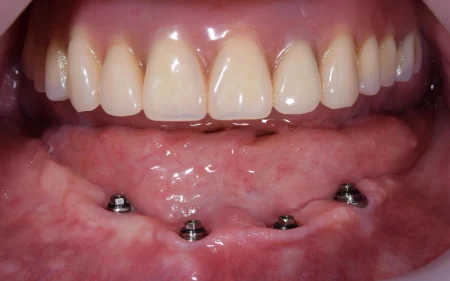

2023.4.17症例インプラント治療症例 No.4

60代男性「歯がどんどん抜けて噛めない」連結した複数の人工歯をインプラントで支える「All on 4」で噛み合わせを改善させ、しっかり噛めるようにした症例

All on 4は、上顎に6本、下顎に4本埋め込んだインプラントで連結した複数の人工歯を支え、取り外しの必要がなくしっかり噛むことができて、見た目も綺麗に仕上がります。

下のAll-on-4の写真です。